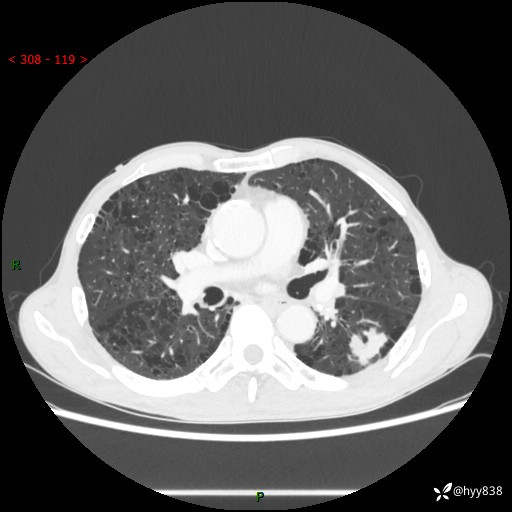

73岁/男,发现肺占位1月余。肺气肿背景,是否恶性倾向---结果公布~

现病史:患者于1月余前无明显诱因出现背部疼痛不适,无明显咳嗽、咳痰、胸闷、咯血、发热等不适,后于2024.5.3至当地市人民医院行胸部CT示:左肺下叶结块,大小约2.2cm*2.6cm,双肺多发小结节,双肺感染性病变,部分纤维增值灶,慢支并双肺局限性肺气肿,肺大泡,纵隔淋巴结增大并部分钙化,冠脉区及大血管壁钙化,双侧胸膜局限性增厚;后口服莫西沙星2周。2024.6.12复查胸部CT示:左肺下叶结块影形态较前饱满,较大截面范围约2.8cm*2.3cm,边缘可见细短毛刺及分叶,性质待查。现患者为求进一步诊治来我院,门诊以“肺占位”收入我科。 起病来,患者精神、食欲、睡眠尚可,大小便正常,体力体重轻微下降。

胸部CT平扫+增强

各期CT值:48hu 100hu 78hu